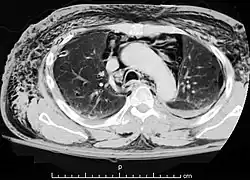

| A CT scan showing air in the mediastinum | |

Pneumomediastinum (from Greek pneuma – "air", also known as mediastinal emphysema)[1] is pneumatosis (abnormal presence of air or other gas) in the mediastinum, the central part of the chest cavity. First described in 1819 by René Laennec,[2][3] the condition can result from physical trauma or other situations that lead to air escaping from the lungs, airways, or bowel into the chest cavity. In underwater divers it is usually the result of pulmonary barotrauma.[1]

Pneumomediastinum is uncommon and occurs when air leaks into the mediastinum. The diagnosis can be confirmed via chest X-ray showing a radiolucent outline around the heart and mediastinum or via CT scanning of the thorax.